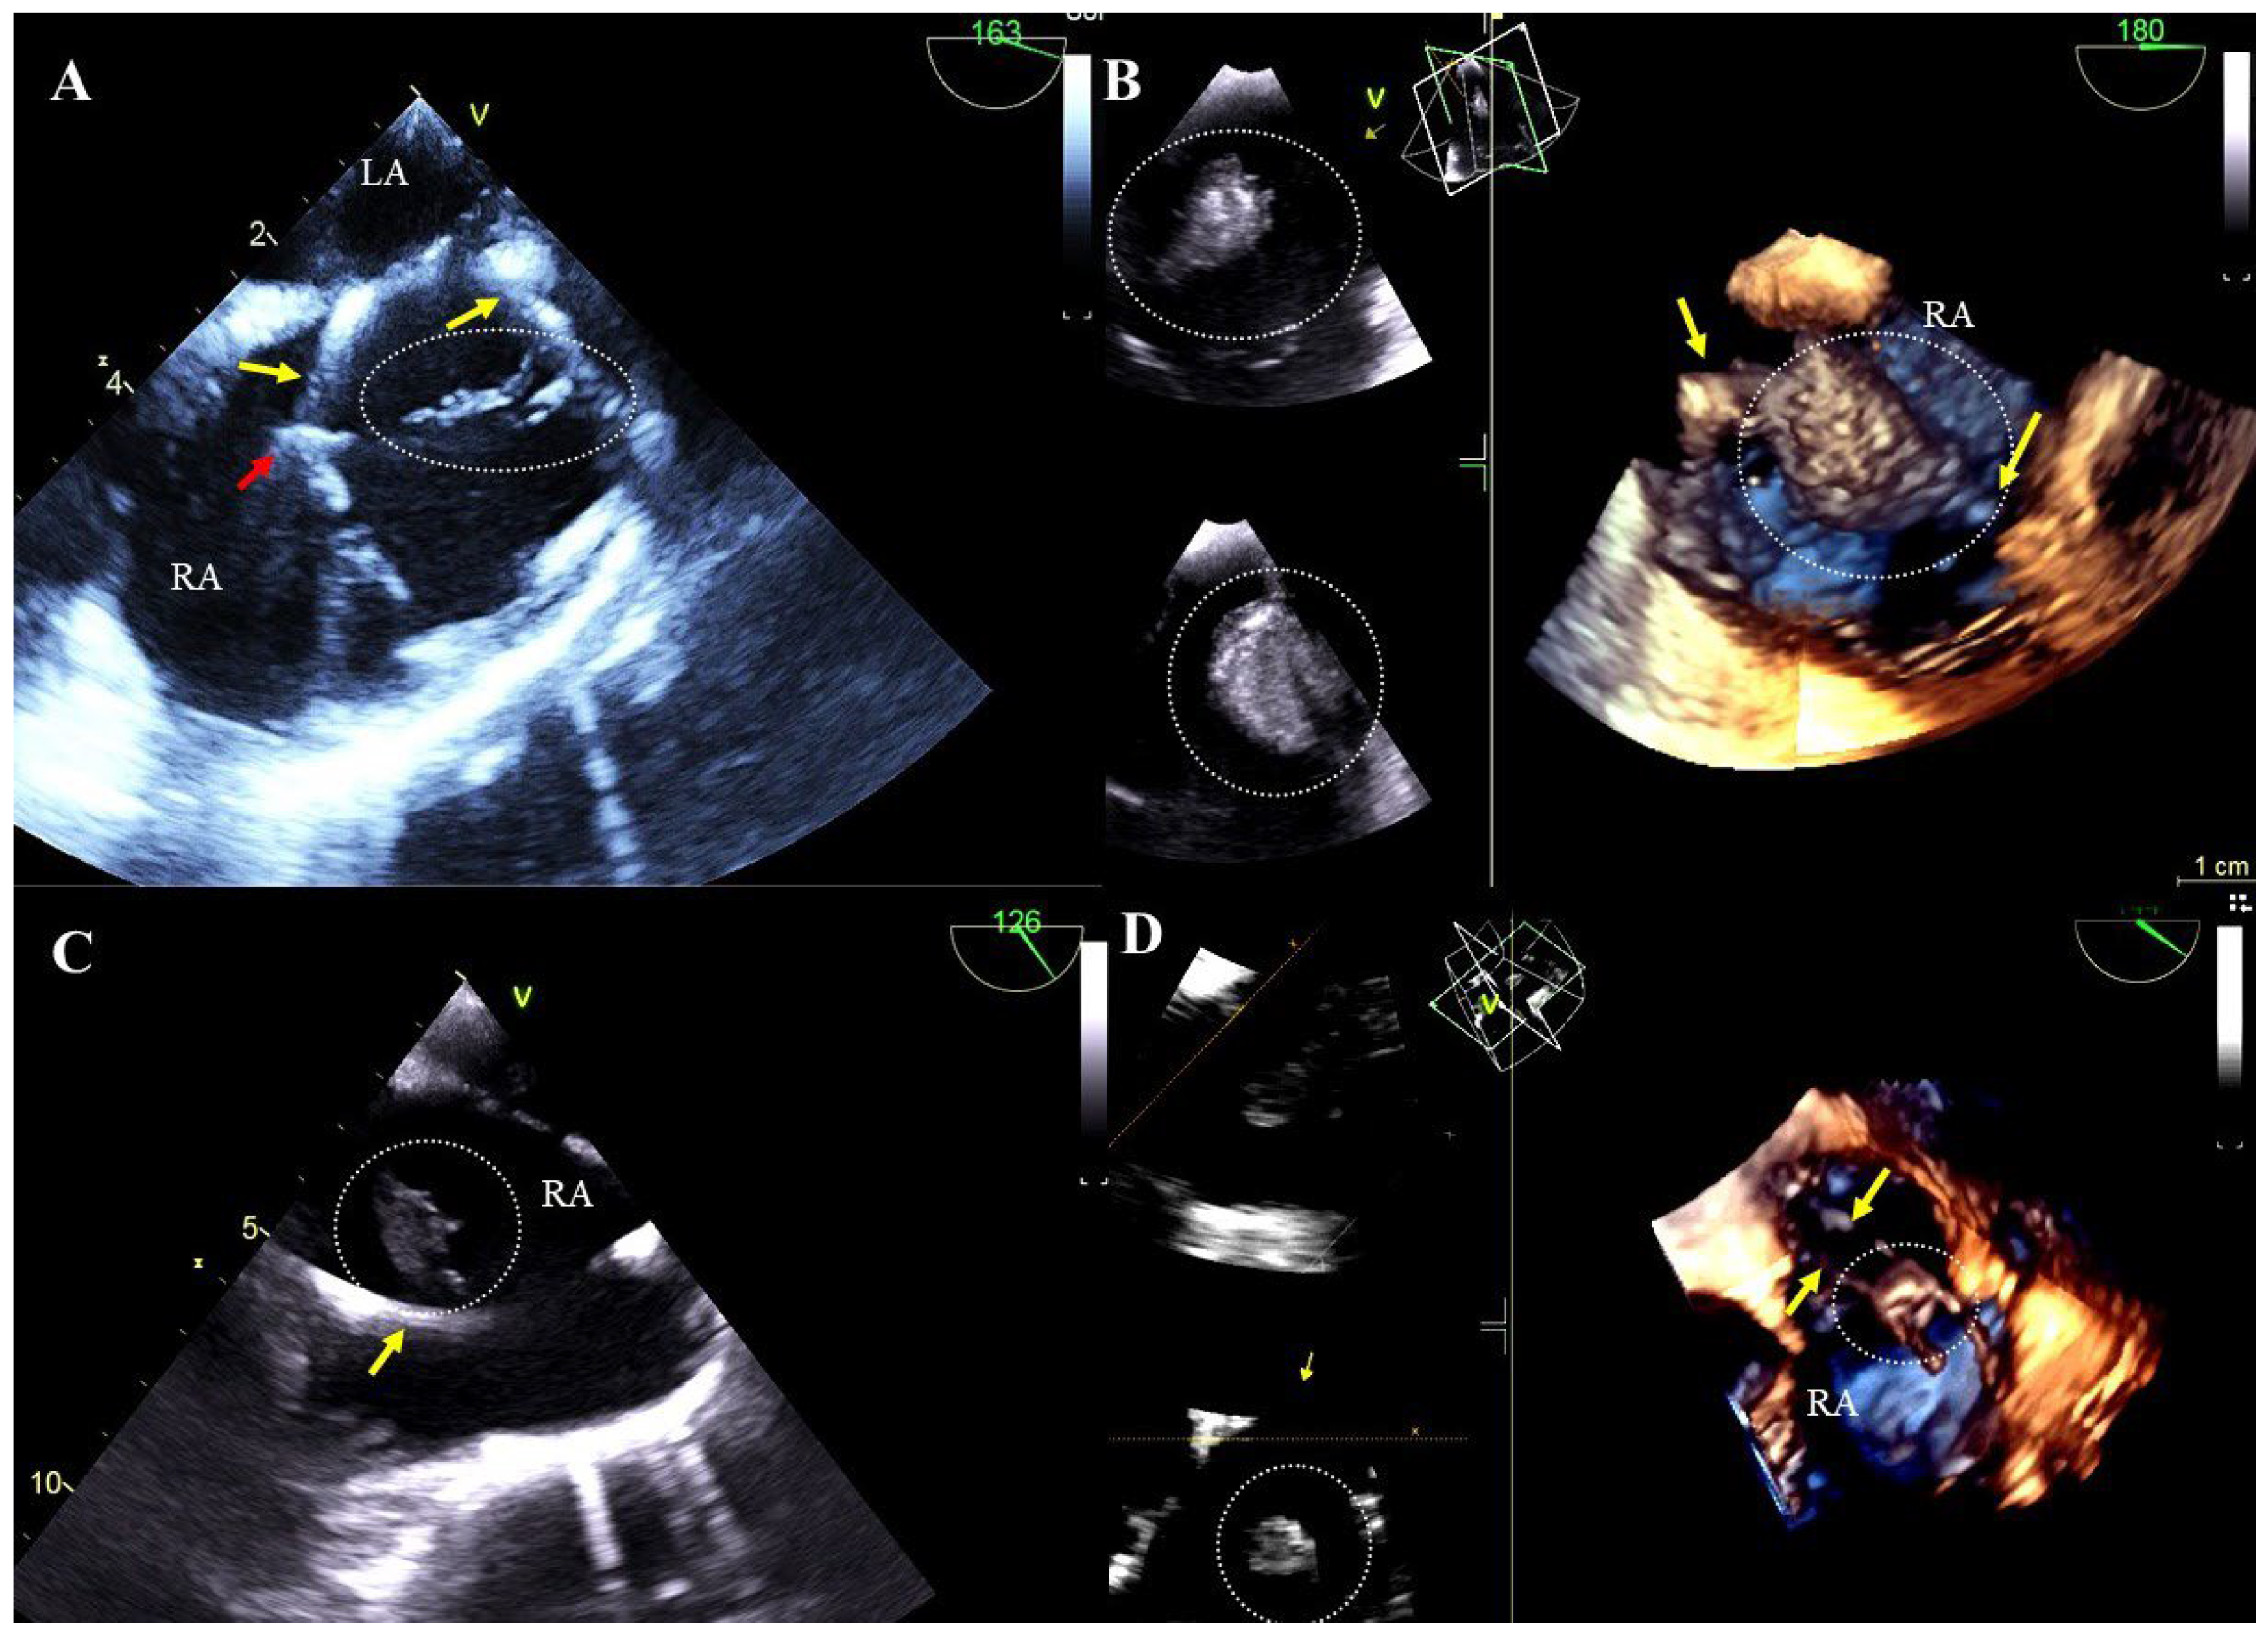

Lead-related cardiac perforation outside the pericardial sac: visualization of the tip of the lead beyond the outline of the heart wall in the pericardial space, often with pericardial effusion (Figure 5A,B, Movie S8).

Excessively long lead loops: excess length of the lead in the heart. Proper lead arcs should not touch the heart wall, especially the TV leaflets, due to the potential risk of adhesion to these structures and their subsequent dysfunction (Figure 5C,D, Movie S10).

Figure 5. TEE (2D, 3D) showing perforations of the heart wall and excess lead loops. The ventricular lead (yellow arrow) perforating the wall of the right ventricle near the apex, visible in the pericardium (red arrow). Separation of pericardial layers—fluid accumulation (green arrow) (A). Perforation of the anterior wall of the right ventricle caused by the lead (red arrow) (transgastric view) (B). A long loop of the left ventricular lead (yellow arrows) dislodging to the pulmonary trunk (C). In the right atrium, tangled loops of two ventricular leads further impair the tricuspid valve function (D).